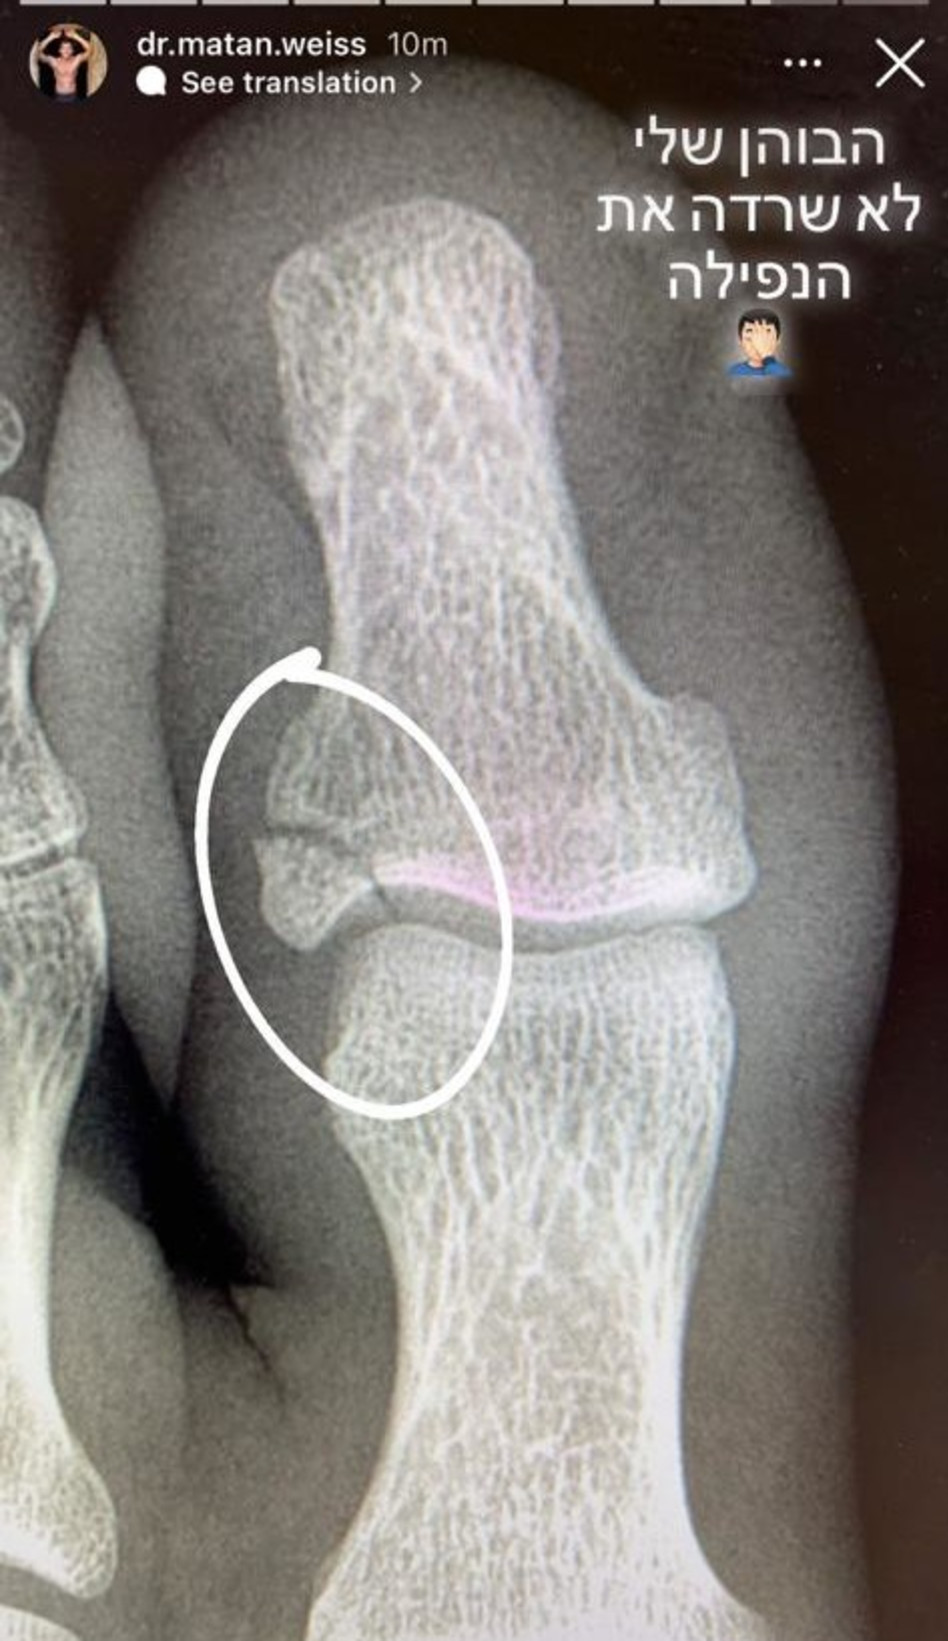

בבית החולים עבר מתן סדרת בדיקות וצילומי רנטגן ונמצא כי הוא שבר את הבוהן בכף הרגל שלו. מתן אף נבחר להיות המטופל הראשון של בית החולים איכילוב שמתנסה במערכת חדשה בה המטופל לוקח מדדים לעצמו והוא התרגש מהמחווה.